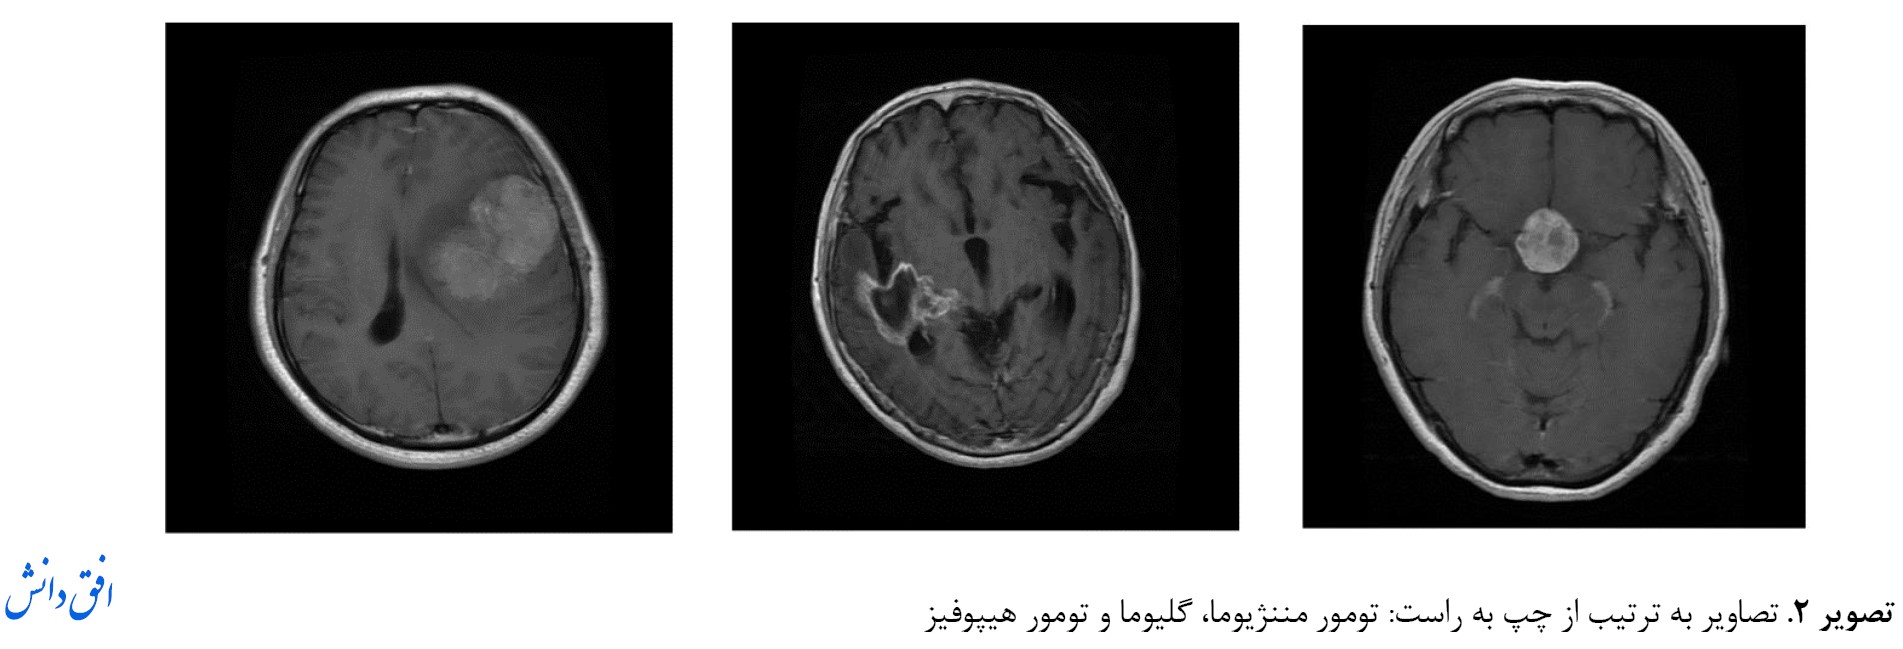

در روش پیشنهادی این مقاله به منظور تشخیص تومورهای مغزی از تصاویر MRI معمولی و استاندارد استفاده شده است. روشهای تصویربرداری MRI دارای پروتکلهای مختلفی هستند که معمولاً برای تحقیقات از پروتکلهای T1 ،T2 و Flair استفاده میشود. به همین منظور از پایگاه داده استفادهشده در این مقاله، که از تصاویر MRI با فرمت 1/5 تسلا هستند و در آنها از پروتکل تصویربرداری MRI-T1 استفاده شده است بهره خواهیم برد. برای این تصاویر پایگاه داده از مرجع [

14] استفاده شده است. در

تصویر شماره 2، سه تصویر از سه کلاس این پایگاه داده نمایش داده شده است.

این پایگاه داده شامل تصاویر سه نوع کلاس مختلف مغزی در ابعاد 512×512 است که سه کلاس آن مربوط به تومورهای مننژیوما (708 تصویر)، گلیوما (1426 تصویر) و هیپوفیز (930 تصویر) است. ابعاد این تصاویر برای استفاده در روش پیشنهادی از 512×512 به 128×128 تغییر داده شده است.